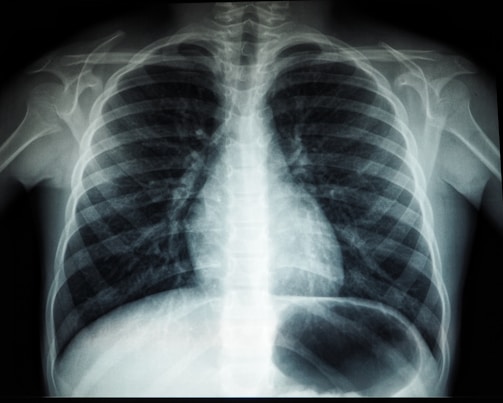

ئێکسڕەی

گرتنی وێنەی ڕوون و ڕاستەقینە بۆ تاقیکردنەوەی تەندروستی.

هەموو جۆرە x-ray بە تازەترین جیهازەکان

جیهازە نوێ

بەکار هێنانی تازەترین سەردۆم